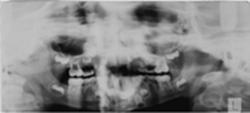

View larger version:

Figure 2

Dental pantomogram of a boy aged 8 years 9 months in the early mixed dentition with unexpected early apical resorption of the entire root complex and partial resorption of the crown of the primary maxillary second molars. Taurodontia is seen in the permanent maxillary first molars and agenesis of all second premolars. A follow-up radiograph (not shown) taken 3 years 8 months later confirmed the findings of dental deviations seen in the first radiograph. Additionally, the mandibular first premolars showed a deviant eruption pattern with resorption of the primary mandibular second molars.